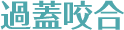

治療方法 上下床矯正装置+インビザライン

(親知らず抜歯)治療の説明 主訴: 右上1と右下1が出ている、叢生 年齢 23歳 ![]()

治療費用 877,800円(税込)

(インビザライン767,800円 床矯正2装置110,000円)治療期間 3年1ヶ月 通院回数 18回 治療の副作用(リスク) 咬合痛、歯根吸収、歯根露出が生じる可能性があります。 歯科医師からのコメント 上下で拡大床装置ありで期間は3年ですが、右上1番の唇側傾斜が改善、しっかり噛めるようになっています。 本人許可 症例写真としてのHPなどへの掲載許可を得ています。